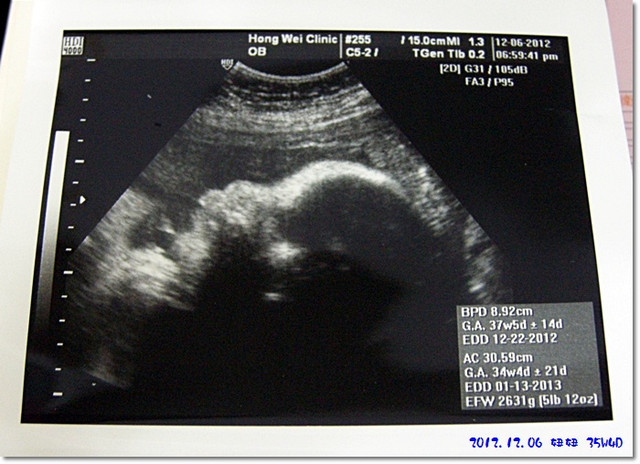

這是這次的超音波圖片...

目前35週,妞妞體重預估為2600g...

一個禮拜只多了100公克,尚可以接受啦(但麻咪好像覺得還是有點點少)

這次來看妞妞,她是測躺在麻咪的肚子裡,感覺躺的挺爽的![]()